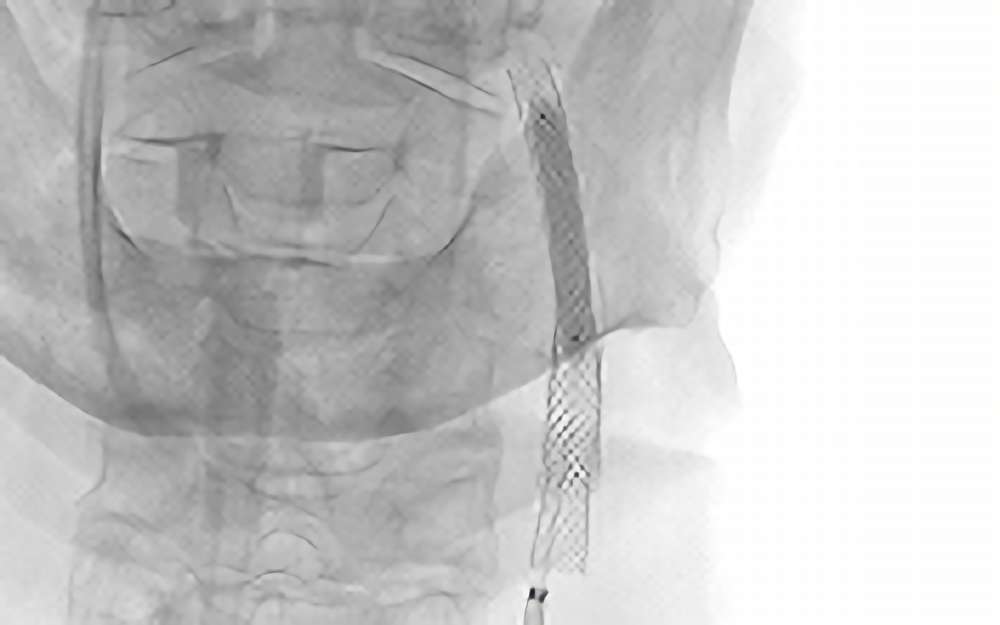

症例 '20年8月 No. 892

左内頚動脈狭窄症

治療中

治療中